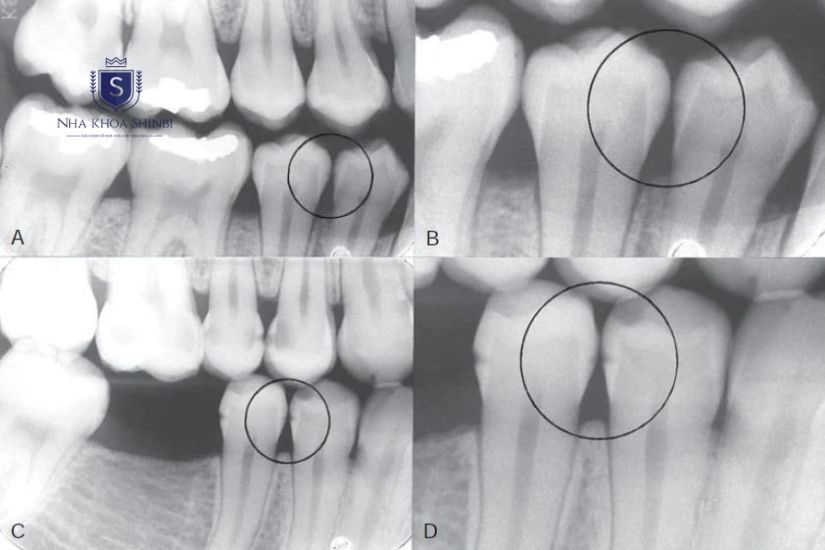

Chụp X-quang răng và lên kế hoạch điều trị

Đầu tiên, khách hàng sẽ được bác sĩ tiến hành kiểm tra tổng quát tình trạng răng miệng để đánh giá mức độ phức tạp của răng cấm cần nhổ. Sau đó, bác sĩ sử dụng công nghệ chụp X-Quang CBCT (Cone Beam Computed Tomography) hiện đại để xác định vị trí, kích thước, hướng mọc của răng, cũng như kiểm tra mối liên quan giữa răng với các cấu trúc quan trọng như dây thần kinh hay xương hàm.

Răng sâu dưới màn hình X-Quang

Dựa trên kết quả khám và X-quang, bác sĩ sẽ tư vấn cụ thể có nên nhổ răng đó hay không, nên thực hiện phương pháp nào, các bước thực hiện ra sao, cũng như những lưu ý quan trọng trước và sau nhổ răng cấm.